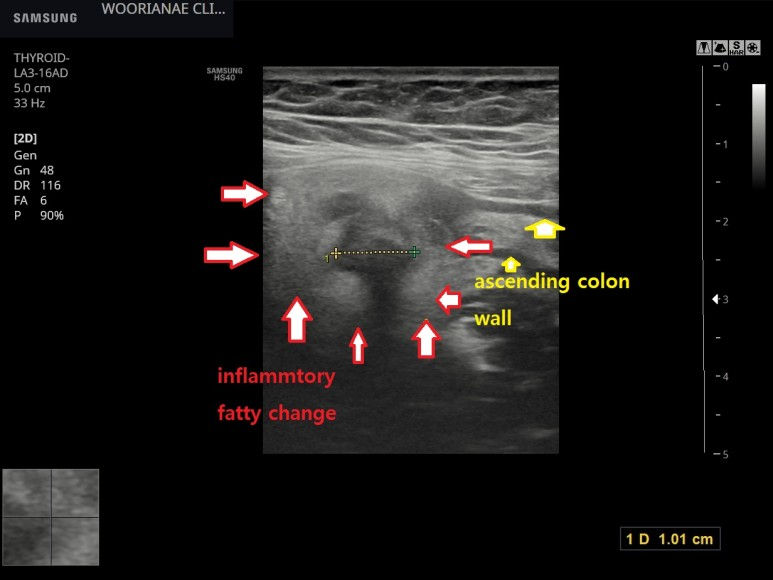

과거 게실염 기왕력, 우측 복통으로 같은 질환 의심하고 내원, 초음파 소견

40대 초반 과거 2회의 게실염 입원력 대장내시경 당시 시행함 "2일간 오른쪽 아랫배가 아프고 걸을때 울린다." 설사/구토 없음 우측 Mcburney point 보다는 위쪽으로 뚜렷한 압통 소견 초음파 시행 정상 충수돌기를 확인하였으며...